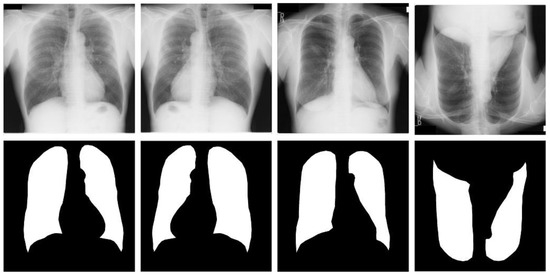

Figure 5.

Images and masks of the Shenzhen dataset.

Shenzhen dataset [18]. This dataset is a collaboration between the Third People’s Hospital of Shenzhen, Guangdong, China, and the National Library of Medicine of Maryland, USA. It contains 662 radiographic images of the human chest region; each CXR radiograph is a single-channel grayscale image with a color depth of 8 and an average resolution of 326 radiographs healthy subjects and 336 from patients with tuberculosis. We used this dataset supervised and labeled by professional radiologists, which was provided by Jaeger et al. [18]. For the Shenzhen dataset, we used simple three-fold machine rotations and a simple three-fold flip data enhancement strategy, and trained the original image data together in the expanded dataset, which was expanded to seven times the original size, containing 4634 images. We use 3710 images as training cases, 336 images as validation cases, and 336 images as test cases. Table 1 shows the CXR and its specification summary of the X-ray film images of the three data sets after data enhancement, and the original and enhanced example images of the three data sets are shown in Figure 3, Figure 4 and Figure 5.